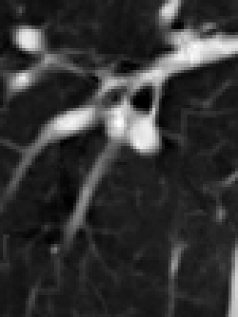

(a) original slice (b) original transform (c) mesh-based compensation (d) block-based compensation

(blurred) (sharp) (more details)

For visual comparison of the lowpass bands of the different approaches, a zoom into one slice of the lowpass band of thorax2 is shown in Figure 2. Compared to the corresponding original slice in Figure 2 (a) the blurriness of the lowpass band of the original transform can be seen in Figure 2 (b). The lowpass bands of the compensated transforms in Figure 2 (c) and (d) represent the structures sharper and more detailed.